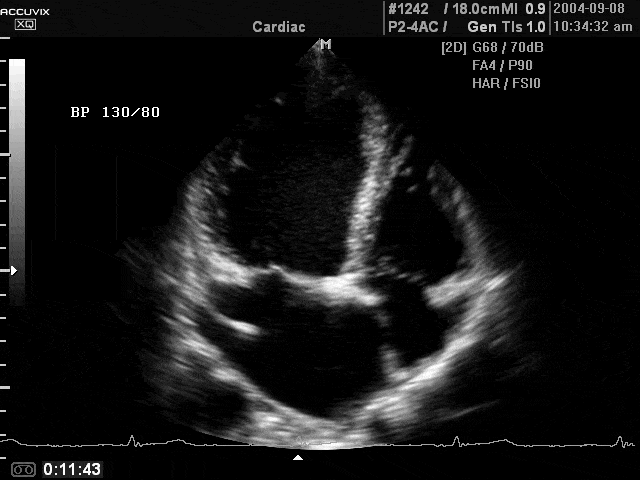

Mitral valve disease, B-mode (echogramm №360)

Echogramm was received by ultrasound scanner Accuvix-XQ (out of production).